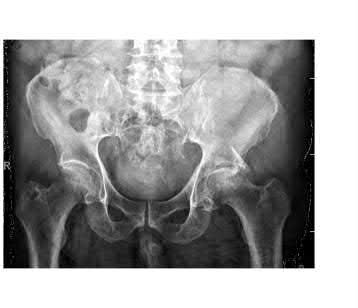

A 44-year-old male presents after being struck by a car. He is hypotensive, and has an obvious open tibia and a closed femoral shaft fracture. A pelvic radiograph is obtained and shown in Figure A. A representative CT scan image in shown in Figure B. The patient is placed in a pelvic binder, and his blood pressure normalizes with crystalloid and a blood transfusion. He then undergoes pelvic angiography, and his internal iliac artery is embolized. Which of the following definitive treatment options is most appropriate in this case?

The radiographs and CT scan show a fracture pattern consistent with an APC-III injury. This is most appropriately treated with pubic symphysis ORIF with a multi-hole plate and posterior iliosacral screw fixation.

APC-III pelvic ring injuries are associated with with disruption of the anterior and posterior SI ligaments (SI dislocation) as well as disruption of

sacrospinous and sacrotuberous ligaments. They are commonly associated with vascular injury and retroperitoneal bleeding.